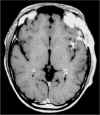

Voluminosa lesione in

sede crtca

Controllo RM

postoperatrio

Astrocitoma talamico

Indagine RM

postchirurgca